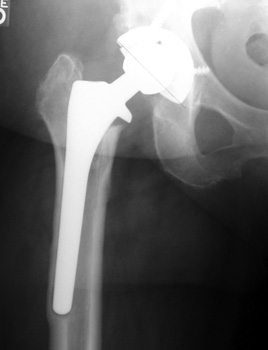

No prior studies available. Abnormally widened interfaces about femoral component at Gruen zones 1, 6, and 7. Osteolysis at Gruen zone 5 with marked thinning of femoral cortex placing patient at risk for pathologic fracture.

Cement fracture Gruen zone 6 close up next slide

SUBSIDENCE - loose femoral prosthesis with interface widening,

osteolysis Gruen zone 6, cement fracture left femoral component

and osteolysis, with femoral component in valgus.